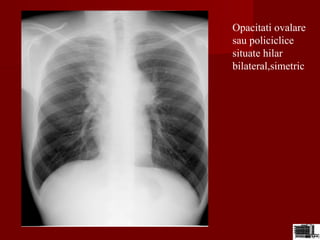

Opacitati ovalare

sau policiclice

situate hilar

bilateral,simetric